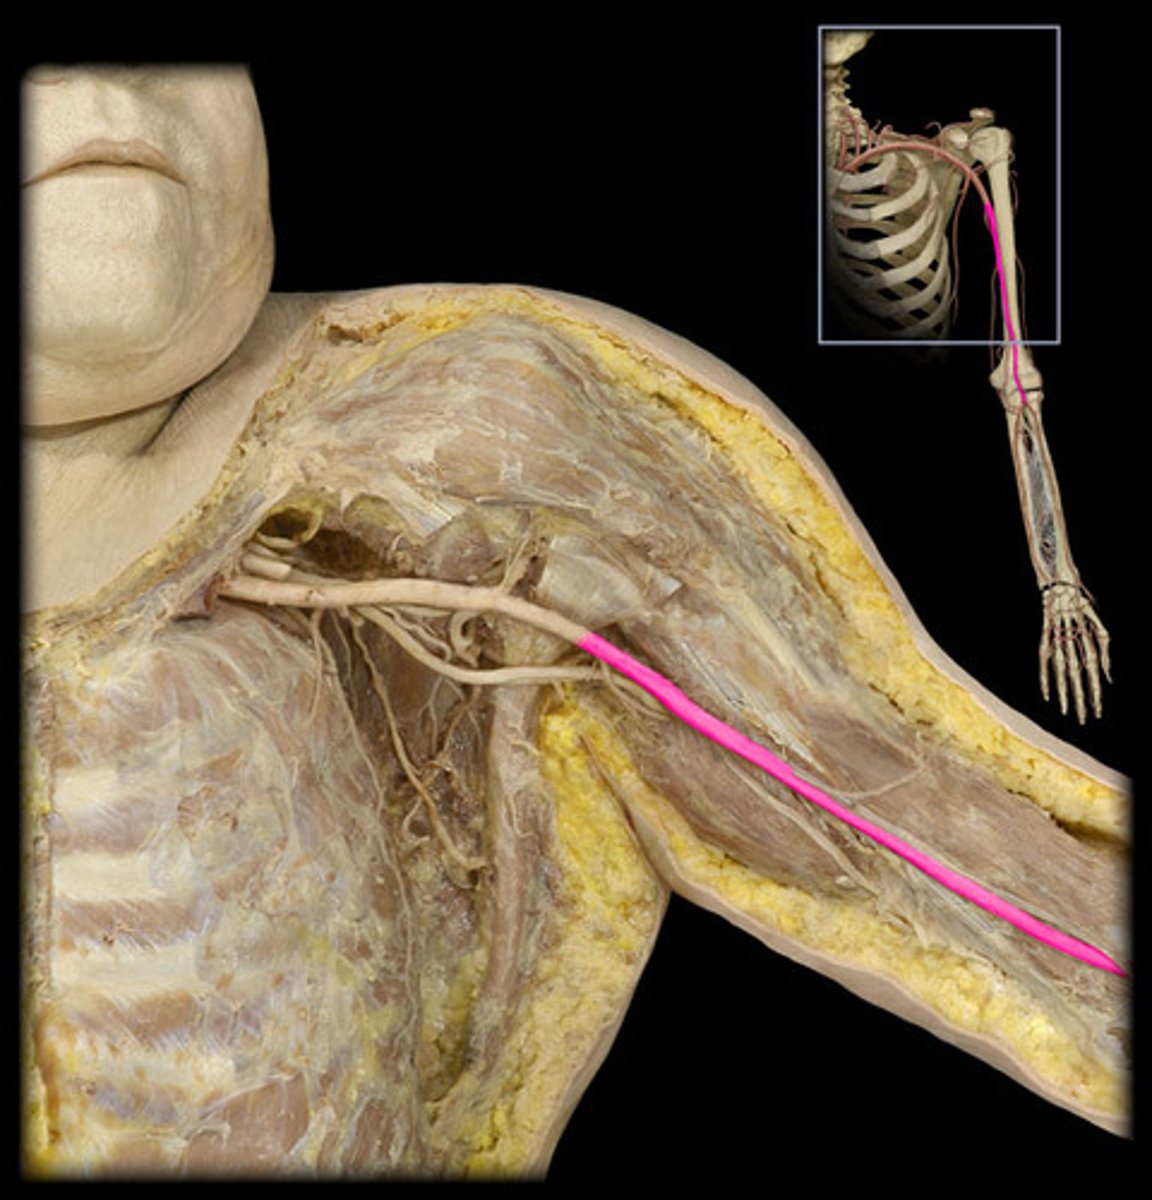

Brachial a.

Name this structure.

Radial a.

lateral forearm

Ulnar a.

medial forearm